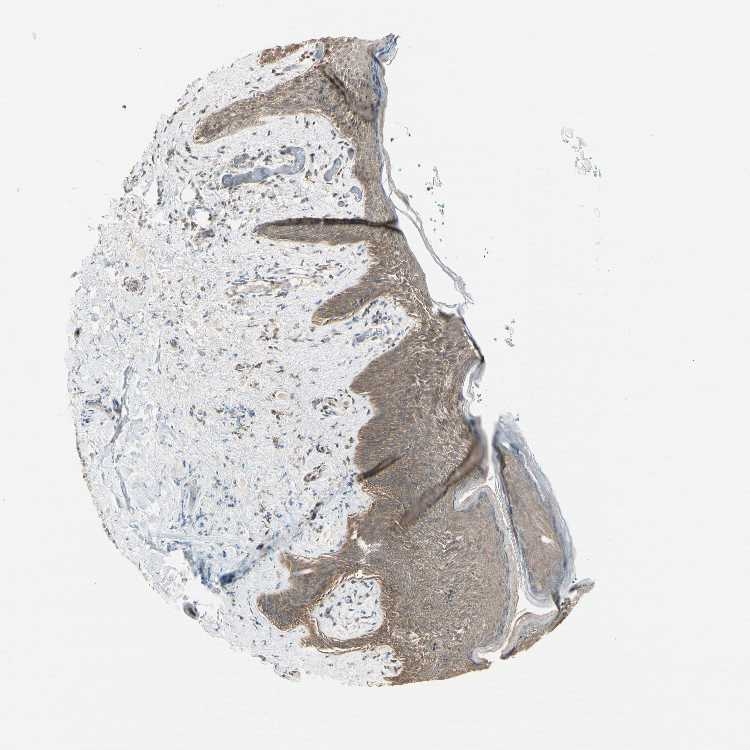

SKIN 1 - Antibody stainingi

Antibody staining in the annotated cell types in the current human tissue is reported as not detected, low, medium, or high, based on conventional immunohistochemistry profiling in selected tissues. This score is based on the combination of the staining intensity and fraction of stained cells.

Each image is clickable and will lead to virtual microscopy that enables deeper exploration of all samples and also displays staining intensity scores, fraction scores and subcellular localization as well as patient and tissue information for each sample.

Antibody CAB010824

Langerhans Low

Fibroblasts Medium

Keratinocytes Medium

Melanocytes Medium